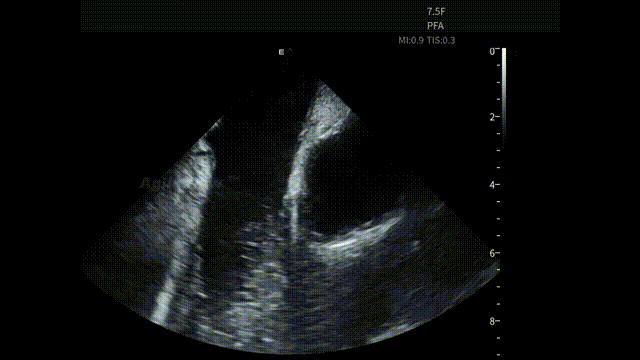

手术开始后,蒋晨阳教授将 AgileView™ 7.5Fr ICE 导管置入右心房,首先通过 HomeView 视角建立心腔整体参照,并对左心耳血栓及心包情况进行系统性评估。术前影像显示心包存在少量积液,为后续操作提供了重要的基线参考。

HomeView

左心耳血栓筛查

术前心包筛查-有少量积液

房间隔穿刺-导丝进入上腔

房间隔穿刺

导丝进LSPV